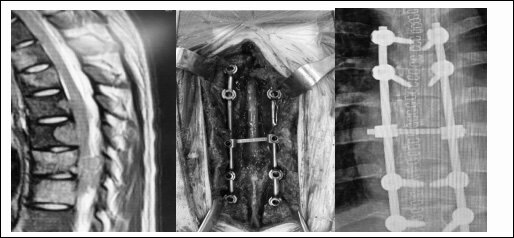

脊柱分离手术在脊柱转移瘤治疗中的病例

病例1、胸椎多节段转移瘤合并椎管内占位、并不全瘫患者,患者卧床1月余,留置导尿。

手术行椎管扩大减压、解除脊髓压迫,重建脊柱稳定性,术后早期即可下床活动,及早开始接受全身治疗。